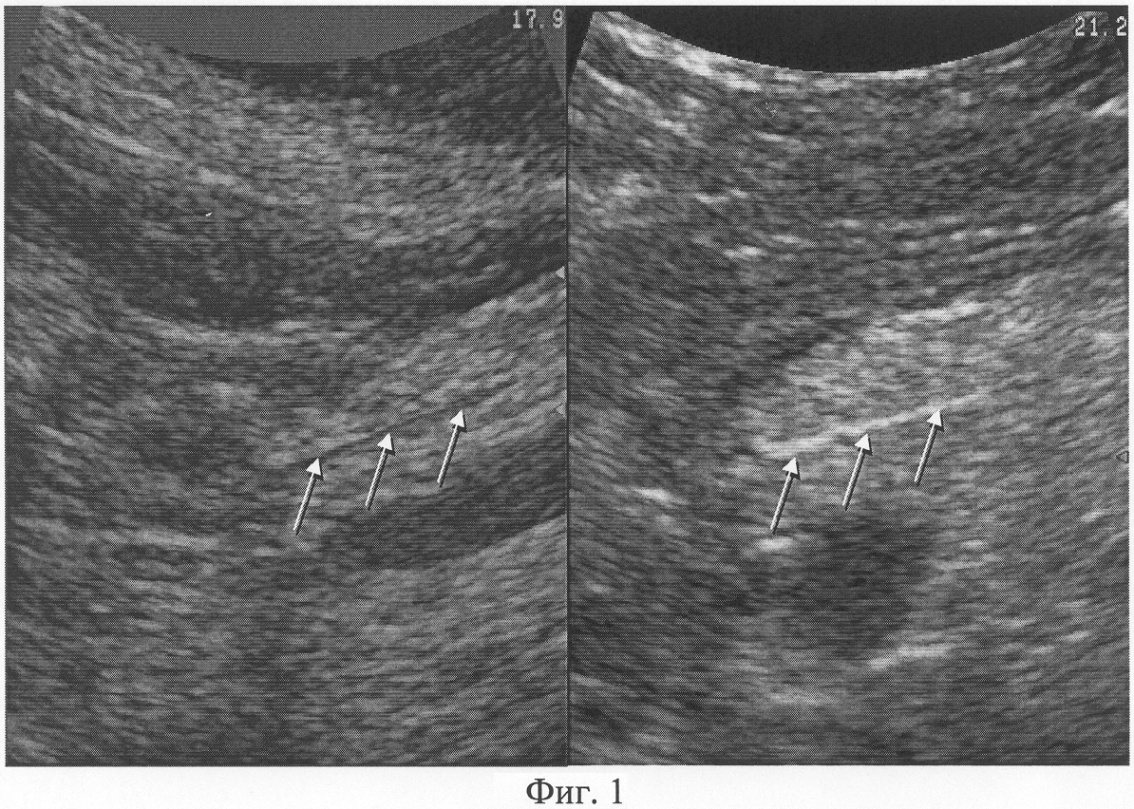

При повышении эхогенности содержимого просвета главного панкреатического протока в сравнении с исходным состоянием вследствие заполнения контрастным веществом главного панкреатического протока определяют наличие дуоденопанкреатического рефлюкса, как показано на Фиг.1.

При осуществлении ультразвукового исследования согласно предлагаемому способу выявлены следующие параметры. Исходно: в просвете главного панкреатического протока на всем протяжении визуализируется однородное анэхогенное содержимое. Осмотр после контрастирования: максимальный диаметр просвета поперечного сечения двенадцатиперстной кишки составляет 22 мм, в ее просвете определяется однородное гиперэхогенное содержимое (контрастное вещество); в просвете главного панкреатического протока на всем протяжении визуализируется однородное анэхогенное содержимое. Заключение: Дуоденопанкреатический рефлюкс отсутствует (фиг.1).